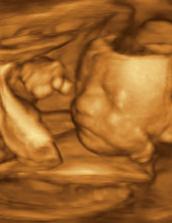

♥ dne 18.9. 3D UTZ - s manželem jsme si móóóc užívali, mrňousek je úúúžasný, takový skříteček..., ale náš 🙂